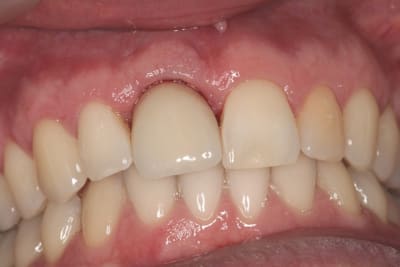

pluton

18/10/2011 à 12h22

joli D57...;-)

çà manque un peu de cas en ce moment...alors en voilà un ptit au passage...

11 avec résorption interne

EII avec MCI sur du dentium (4.5/14) comblement du gap vestibulaire avec du kasios tcp (très constant dans les résultats...et très économique)

pas de photos de chir par contre...j'ai du les effacer par erreur...grrrr...

la prothèse d'usage a été réalisée par ma petite associée...mais j'étais là pour superviser et faire quelques photos...;-)